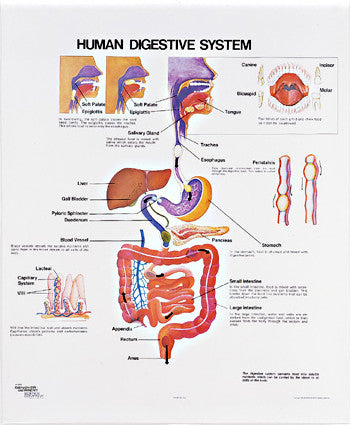

Anatomy

Anatomical models and charts by Body System or Anatomical Region for Nursing, Physical Therapy, and Medical Education.